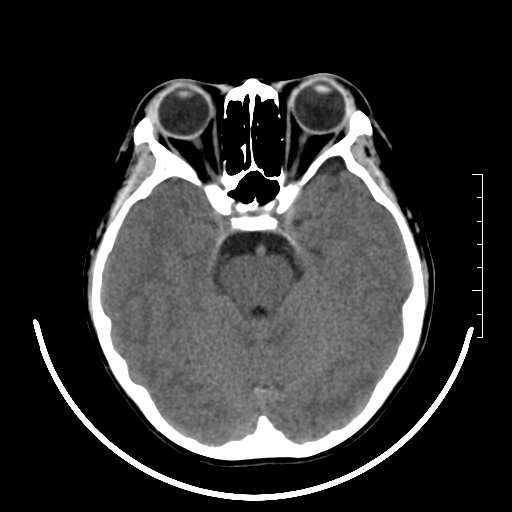

标题: PED3377:m、9y,恶心、呕吐,每月发作2-3次。 [打印本页]

标题: PED3377:m、9y,恶心、呕吐,每月发作2-3次。

右侧基底节区见钙化灶

右侧壳核多枚点状钙化灶。去请结合临床。

右侧壳核多枚点状钙化灶,请结合临床。

右侧壳核多发钙化灶,请结合临床。